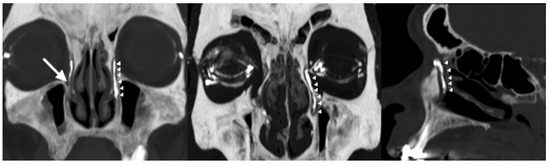

Background: Conventional CT–dacryocystography (CT-DCG) requires canalicular cannulation and forced contrast injection, which may distort anatomy and cause discomfort. This study describes a non-cannulated CT-DCG protocol using dropwise iodixano...